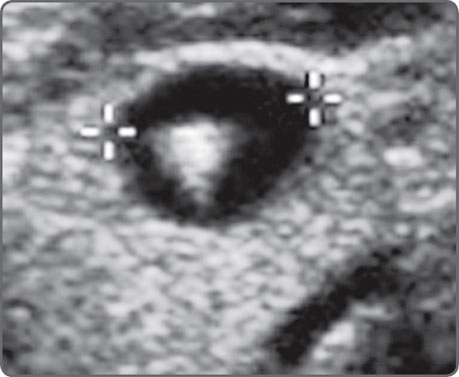

Adjusting gain alters how the transducer perceives returning echoes. Increasing the gain brightens the display of the returning echo information. Gain may be adjusted for the entire image (overall gain), or at depth, known as time-gain compensation (TGC).3 Excessive gain makes the image too bright, and too little gain makes it dark (Figs 2A and B). Excessive gain can make the picture bright with noise. This can obscure fluid echoes (Figs 3A and B). Too little gain may create fluid echoes where no fluid exists (Figs 4A and B). Many currently available medium and high-end units now have a one-touch image optimization button that works automatically to fix the gain in an image.

Figs 4A and B: Inadequate gain can “create” fluid where none exists. In the image on the left (A); a large fluid collection is evident in the right adnexa. Increasing the gain [right (B)] reveals an ovary with three antral follicles